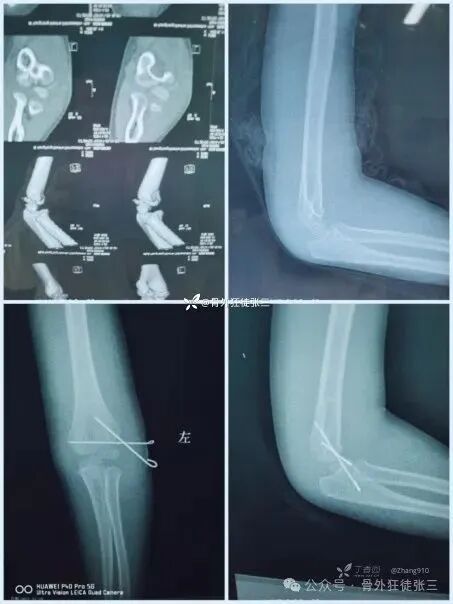

病例11,桡侧三枚针发散固定

6周拔针,关节僵硬

入院康复锻炼1周

12周来院复查

肘关节功能良好

病例12,交叉针